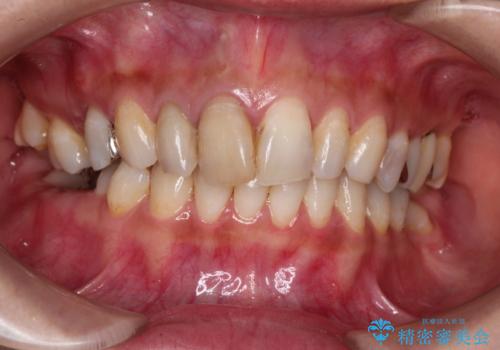

[ セラミック・インプラント全顎治療 ] 長年悩まされている歯の治療にケリをつけたい

![[ セラミック・インプラント全顎治療 ] 長年悩まされている歯の治療にケリをつけたいの症例 治療前](https://seimitsushinbi.jp/wp/wp-content/uploads/2022/01/699ba08b6e311b07f9d2ea9a5b757aea-500x350.jpg?v=1642042101)